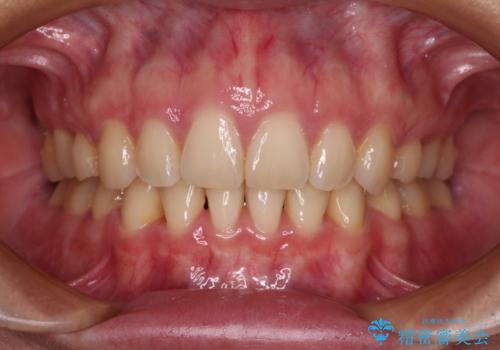

むし歯や銀歯が気になる 後戻りの再矯正治療とむし歯治療